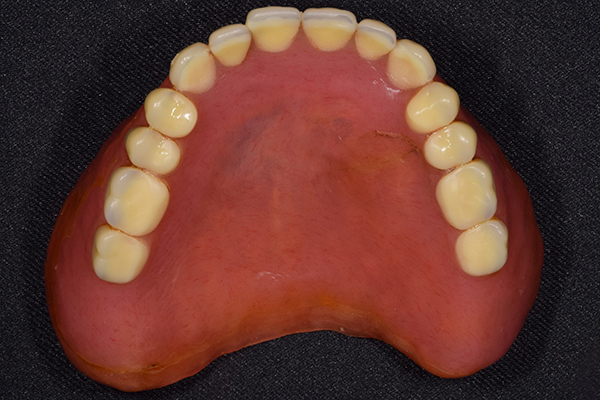

ケース2(自費の総入れ歯と部分入れ歯)

上下の入れ歯が外れやすくなったということでいらっしゃいました。 顎の骨はしっかりしていましたので、精密な型取りさえすればしっかりした入れ歯がつくれると思いました。 また下には6本歯が残っていましたが、虫歯になっている歯もありました。 かぶせ物のなかで大きな虫歯があった歯があり、1本だけ残せない状態でした。

上の入れ歯は確かに吸着は甘くなっていました。 また下の入れ歯はバネの一部が壊れており、安定感がなくなっていました。

精密な型取りの後、噛み合わせのチェックをしていきました。 かぶせ物も同時に作っていきました。

歯を並べた後、かぶせ物のフレーム作ってもらいました。先に歯を並べて理想の位置を決めておくことが大切です。

完成した入れ歯とかぶせ物です。 入れ歯への寛容度が高い患者様でしたので、 金属は使用せず、プラスチックのみで上は仕上げました。 下顎も歯は1本減ってしまいましたが、しっかり 入れ歯が維持できる様な構造にしました。

お口の中に入れた状態です。 見た目も最初とほとんど変わることなく作成できました。 維持や吸着に関しても問題ないようでした。

年齢 80歳・女性

主訴 上下の入れ歯が外れやすくなった

治療期間 3ヶ月

治療費 .メタルボンドクラウン:550,000円

.義歯:990,000円(税込、上下)

治療方針 長年使ってきた義歯の人工歯が磨耗し、臼歯部での咬合がすくなくなり、入れ歯の安定も悪くなり、あたりどころが悪くなって痛みが出ている。 そのため、入れ歯を上下作りかえる必要がある。

治療内容 過去に治療を行ったことのある歯が再度虫歯になってしまっているところがあり、すでに残せない状態にまでなっていたため、歯を一本抜歯した。 その後、かぶせ物と入れ歯を同時に作成していった。

特記事項 歯を抜いた後は、2〜3ヶ月歯ぐきの回復を待ってから入れ歯を作るため、待機期間があります。その間、古い入れ歯を調整しながらそのまま使うか、新し物をつくっておく必要があります。ただし、入れ歯は保険治療で作成する場合、6ヶ月は新しいものが作れないという決まりがあるので保険で全て作りたい場合は注意が必要です。